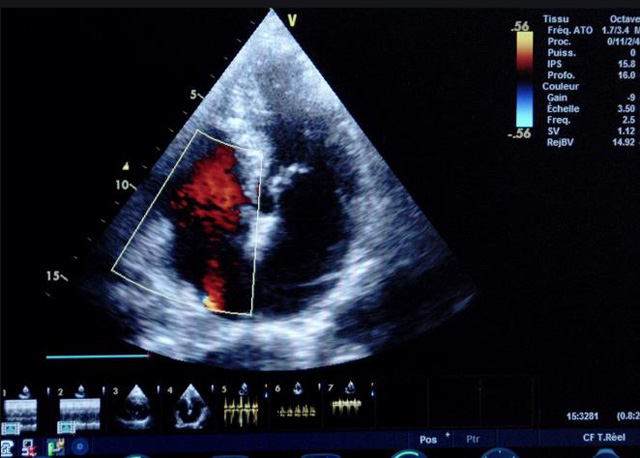

二、彩色室壁運(yùn)動(dòng)分析

(一)基本原理彩色室璧運(yùn)動(dòng)分析,從整體散射數(shù)據(jù)中識(shí)別心內(nèi)膜邊界,并與前一幀彩色不同,心臟收縮或舒張期開始到結(jié)束時(shí)心內(nèi)膜的全部過程。每一次順序顯示結(jié)束后,原來的彩色自動(dòng)消失,以便進(jìn)入下一個(gè)顯示過程。其結(jié)果是獲得對(duì)應(yīng)于每一個(gè)心動(dòng)周期的彩色顯示,描繪特定周期內(nèi)室壁運(yùn)動(dòng)的時(shí)間運(yùn)動(dòng)軌跡。

(二)操作步驟根據(jù)背向散射數(shù)據(jù)中將心內(nèi)膜運(yùn)動(dòng)的位移過程分類為組織或血液的原理,邊緣檢測(cè)跟蹤心內(nèi)膜和血液的界面。橙色表示收縮期的開始,收縮期不同時(shí)相逐幀顯示色彩均疊加在收縮末期最后一幀圖像中。檢查時(shí),可按以下步驟進(jìn)行:

①顯示較為理想的二維圖像,常用切面有心尖四腔心、二腔心、左心室長(zhǎng)軸和左心室乳頭肌水平短軸切面。

②啟動(dòng)AQ系統(tǒng),啟動(dòng)后適當(dāng)?shù)卣{(diào)節(jié)增益補(bǔ)償,顯示心內(nèi)膜。

③啟動(dòng)CK系統(tǒng),啟動(dòng)后劃定感興趣區(qū)域。同時(shí)記錄的心動(dòng)圖R波頂點(diǎn)為舒張末期,T波終點(diǎn)為收縮末期,顯示RT間期的CK彩階圖,連續(xù)記錄3~ 5個(gè)心動(dòng)周期。